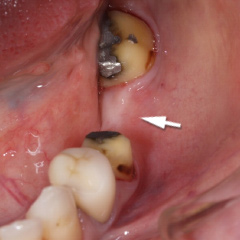

| 歯周病が進行したケースでは盲目下でポケット内の歯石を確実に除去するには限界があります。 | 局所麻酔をした後、歯茎を切開し、明視下にて歯根面の歯石や炎症組織を取り除き、歯周ポケットの除去をおこないました。 |

| 深い虫歯のケースでは、切除療法を行い虫歯を取り除き、健全な歯質を歯肉の上に出し、歯肉の盛り上がりを数ヶ月待ってから歯型をとります。 |

| 一見分りませんが、かなり歯周病が進行していました。歯周ポケットの改善や歯槽骨を平坦にして清掃しやすい環境を整えます。数ヶ月、歯肉の盛り上がりを待ってから適合の良いクラウンを被せます。 | ||